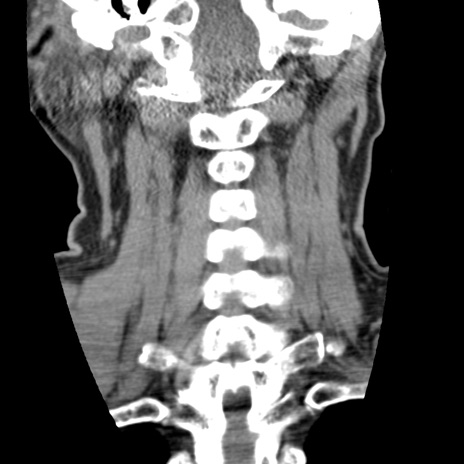

症例50 頚椎CT(冠状断像)

頚椎CT